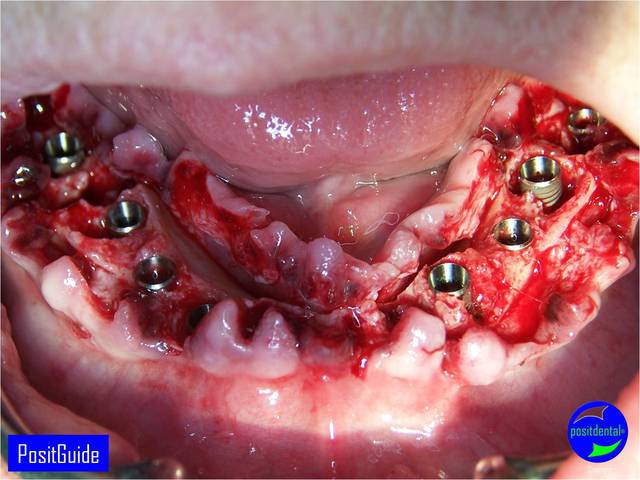

Mise en Charge Immédiate Post Extractionnelle , MCIPE partie chirurgicale de A à Z

implants in situ et S.I.A.O pré-opératoire